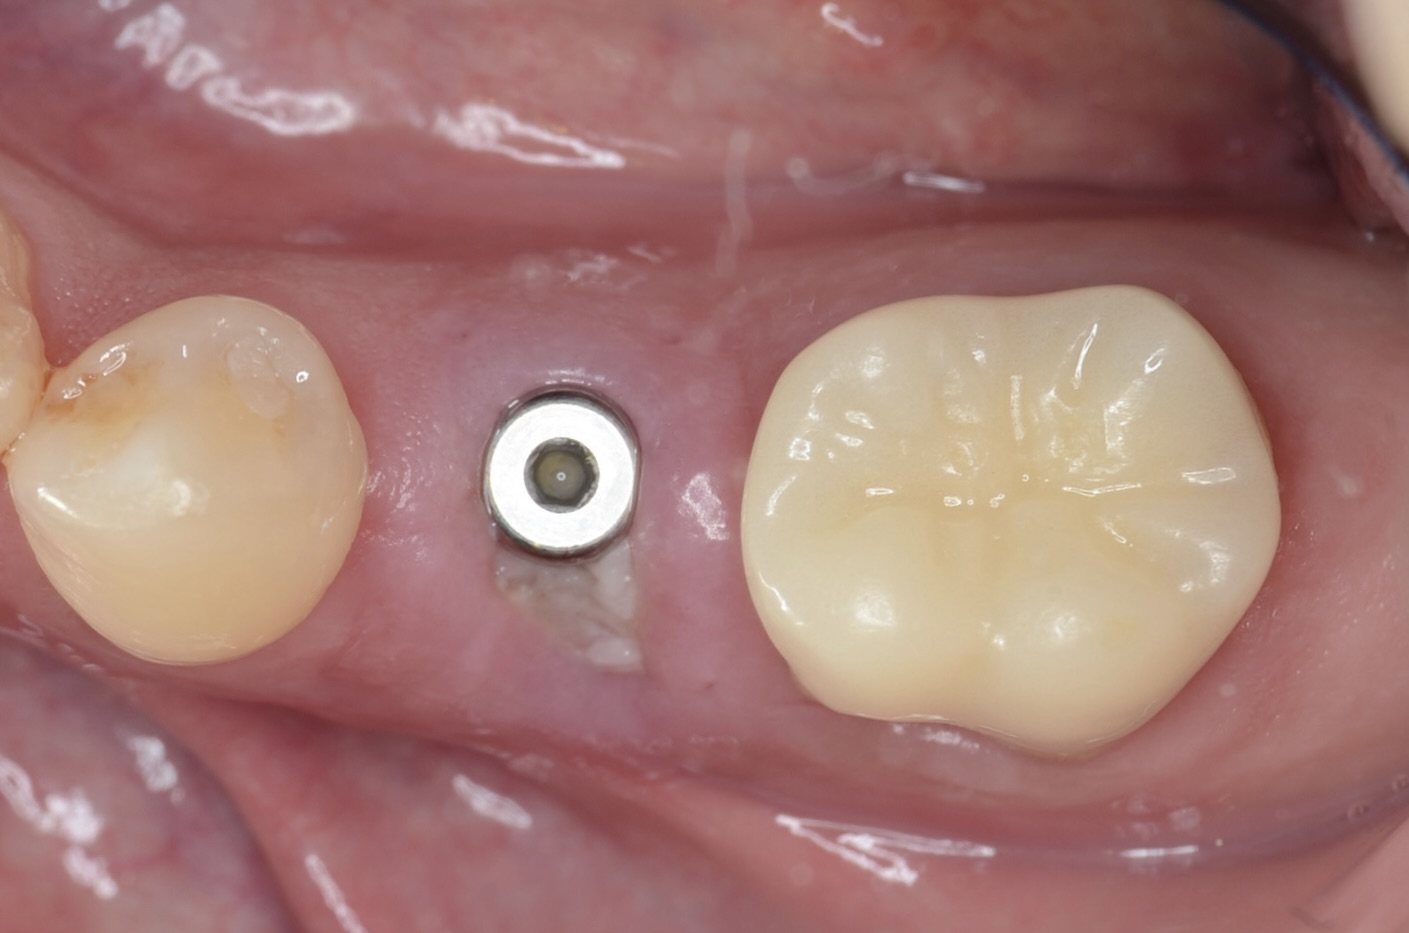

術後1週間

抜歯即時埋入は、痛みや腫れが少ないです。 -